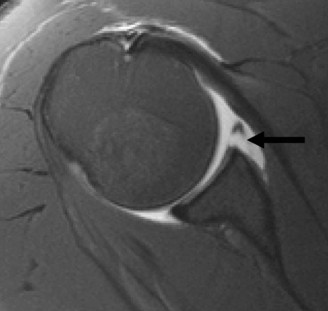

The correct answer is (A). In a young patient, the most likely injury associated with a glenohumeral dislocation is a labral tear (see Fig. 2–31). In an older patient, >40 years old, a rotator cuff tear is more likely. Other possible associated injuries include:

Figure 2–31 MRA demonstrating an anterior labral tear.